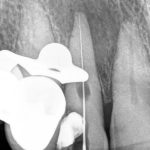

En una segunda cita pasamos al siguiente peldaño del tratamiento. Procedimos a retirar todos los materiales intraconducto y obturar. Para ello, en primer lugar, se realiza el Downpack con System B para sellar el tercio apical. A continuación, con la técnica de inyección de gutapercha, se rellena el tercio medio y coronal del conducto de la pieza 1.2, con el consiguiente sellado de la cavidad de la reabsorción.